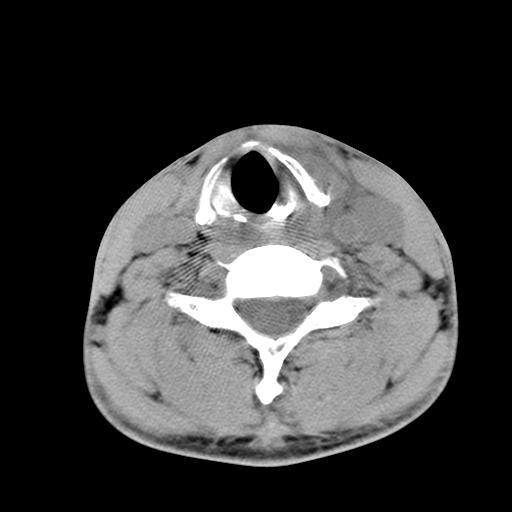

标题: CT15118:f-27y,左颈部肿一个月,无发热、无压痛 [打印本页]

标题: CT15118:f-27y,左颈部肿一个月,无发热、无压痛

1、甲状腺左叶病变:腺瘤?结节性增生?其他?

2、上极周围间隙病变。

3、2者关系?

左侧甲状腺肿大,密度不均.同侧甲状软骨似有破坏(建议传骨窗).左侧颈静脉增粗,各组织之间分界不清,有多个肿大淋巴结.甲状腺肿并感染?临床症状不符.淋巴结核?请结合其他检查.